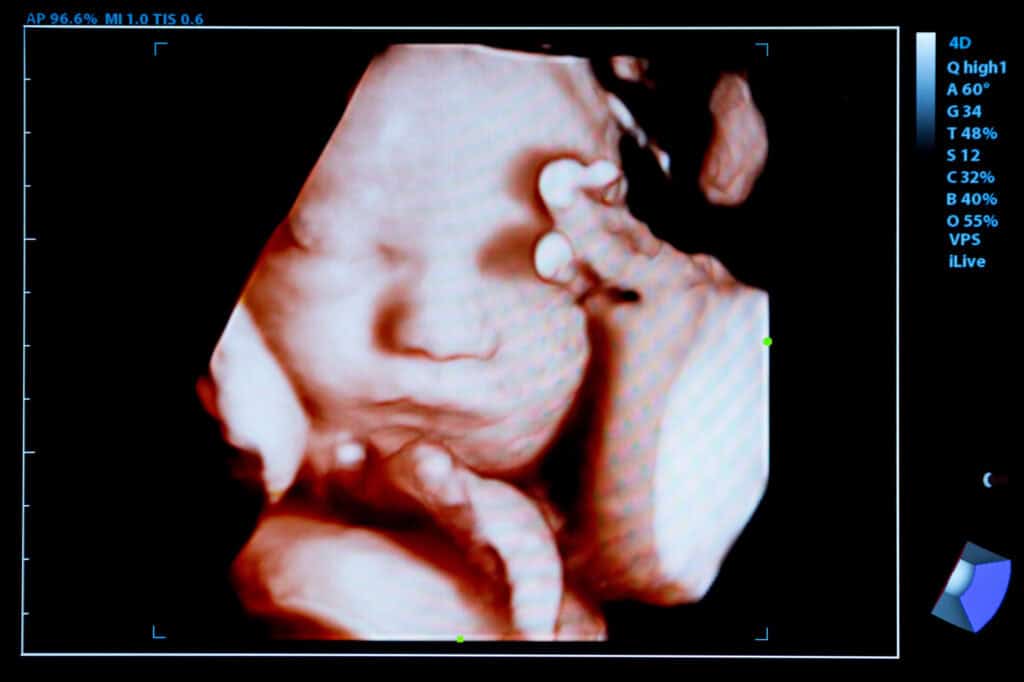

|Multiple Ultrasound Pictures

Supreme Court Shown Baby with 4D Ultrasound, Urged to Uphold Mississippi’s 15-Week Abortion Ban

They say a picture is worth 1,000 words. And one organization is betting that showing the U.S. Supreme Court a 4D ultrasound picture of a...